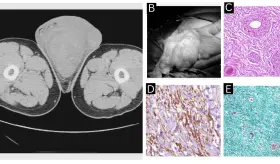

Las prótesis antiguas de metal con metal pueden liberar partículas mic...

Los tumores presentaron un patrón histológico casi idéntico y localizado en el área de contacto directo con el dispositivo, lo que sugiere un posible efecto relacionado con la exposición prolongada a la radiación electromagnética.